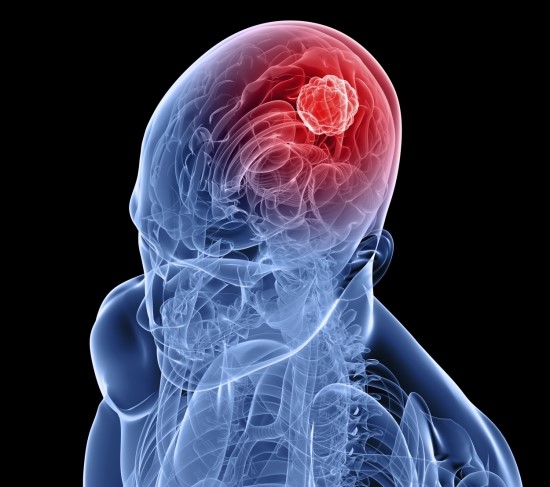

뇌종양은 뇌조직이나 뇌를 싸고 있는 막에서 발생된 종양과 머리뼈나 주변 구조물에서 멀리 떨어진 부위에서 뇌조직이나 뇌막으로 전이된 종양을 말합니다. 또, 뇌종양은 양성과 악성으로 나눌 수 있는데요. 양성 뇌종양은 성장속도가 느리고 주위 조직과의 경계가 뚜렷한 특성을 지니고 있습니다. 악성 뇌종양은 뇌암이라고도 말하며, 성장속도가 빠르고 주위 조직으로의 침투 능력이 강하여 주변의 정상 뇌조직을 빠른 속도로 파괴합니다.